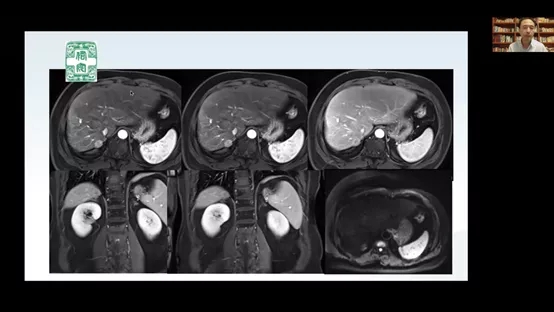

教学查房由北京佑安医院中西医结合中心、“双首”健康行动中医传染病团队负责人李秀惠教授发起,北京佑安医院中西医结合中心李丽主任医师主持,查房病例为中西医结合中心1例“原发性肝癌术后10年余伴肾上腺转移”患者的诊治资料。教学查房首先由主管医师汇报病例,北京佑安医院肝病肿瘤介入中心导管室崔雄伟主任、北京佑安医院中西医结合中心李丽主任医师、李秀惠教授分别讲解了该病例的放疗和介入治疗、肝癌靶向治疗、全程中医药治疗的过程、经验和知识拓展,参会人员包括佑安医院中西医结合中心团队、呼和浩特市第二医院的中医团队,同时还邀请了河北秦皇岛市第三医院、山西太原市第三人民医院、山东青岛第六人民医院、西南医科大学附属中医医院的中医团队参与了讨论,参会总人数近50人。